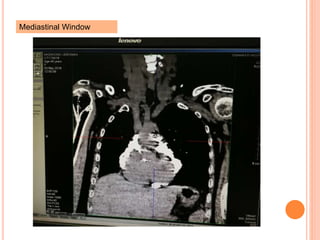

Mediastinal Window